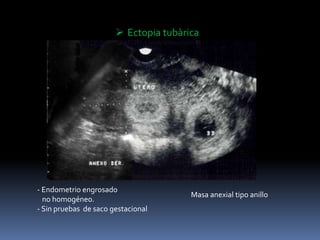

 Ectopia tubarica

- Endometrio engrosado

no homogéneo.

- Sin pruebas de saco gestacional

 Ectopia tubàrica

Masa anexial tipo anillo